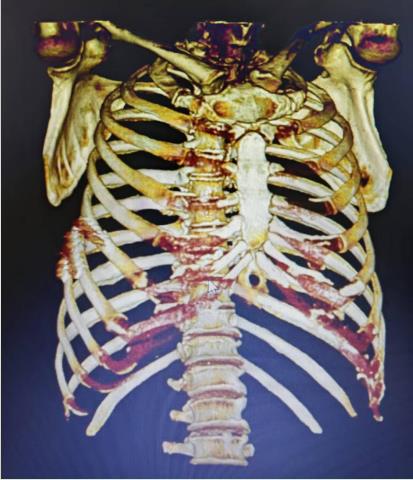

• 骨创伤治疗仪联合胸腔镜下肋骨骨折内固定手术治疗多发肋骨骨折合并血气胸的临床疗效

2025, 31(12):33-42. DOI: 10.12235/E20240685

摘要 (86) HTML (51) PDF 5.26 M (84) 评论 (0) 收藏

摘要:目的 探讨胸腔镜下肋骨骨折内固定术后,辅助给予骨创伤治疗仪,治疗多发肋骨骨折(MRF)合并血气胸的临床疗效及安全性。方法 选取2021年1月-2024年1月该院收治的MRF合并血气胸患者86例,采用随机数表法将患者分为两组,各43例。两组均接受胸腔镜下肋骨骨折内固定手术治疗,对照组于术后给予常规处理,观察组在对照组基础上,接受骨创伤治疗仪辅助治疗。观察两组患者近期和远期疗效。比较两组患者术前、术后3 d、术后7 d和术后14 d的血胸出血量和疼痛视觉模拟法(VAS)评分。比较两组患者术前和术后14 d的凝血功能指标[凝血酶原时间(PT)、活化部分凝血活酶时间(APTT)、凝血酶时间(TT)、纤维蛋白原(FIB)和D-二聚体(D-D)]。比较两组患者术后恢复情况(引流管留置时间、肿胀消退时间、住院时间和骨折愈合时间)和术后并发症发生情况。结果 观察组近期疗效总有效率为97.67%(42/43),明显高于对照组的81.40%(35/43),差异有统计学意义(P < 0.05)。观察组远期疗效总有效率为97.67%(42/43),与对照组的88.37%(38/43)比较,差异无统计学意义(P > 0.05)。术后3、7和14 d,两组患者血胸出血量明显少于术前,且观察组明显少于对照组,两组患者疼痛VAS评分明显低于术前,且观察组明显低于对照组,差异均有统计学意义(P < 0.05)。术后14 d,两组患者PT、APTT和TT明显长于术前,且观察组明显长于对照组,两组患者FIB和D-D明显低于术前,且观察组明显低于对照组,差异均有统计学意义(P < 0.05)。观察组引流管留置时间、肿胀消退时间、住院时间和骨折愈合时间明显短于对照组,差异均有统计学意义(P < 0.05)。观察组术后并发症总发生率为2.33%(1/43),与对照组的11.63%(5/43)比较,差异无统计学意义(P > 0.05)。结论 胸腔镜下肋骨骨折内固定术后辅助给予骨创伤治疗仪治疗,能有效地促进MRF合并血气胸患者胸腔积气和积液的吸收,减轻疼痛程度,改善凝血功能,加快术后机体恢复。值得临床推广应用。